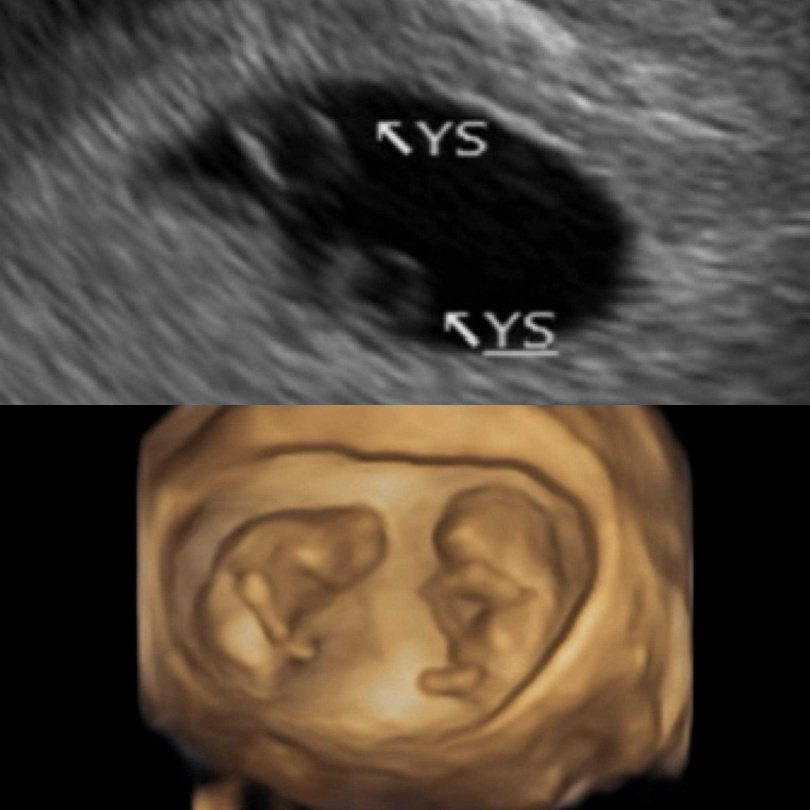

她回憶,產檢期間透過超音波檢查,意外得知懷上雙胞胎。由於屬自然受孕的同卵雙胞胎,讓她在驚喜之餘也伴隨擔憂。直到懷孕6週聽見胎兒心跳後,情緒才稍稍放下,坦言當下因想起前次未能聽到心跳的經歷,忍不住落淚。

鄭家純懷孕12周。(圖/翻攝臉書/鄭家純)

目前懷孕已滿12週,鄭家純也公開10週時的超音波影像,透露兩名胎兒位置特殊,外觀如太極圖形。她表示,現階段正以較平穩心情面對身體變化,迎接接下來的孕期生活。